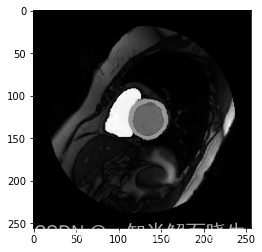

这个笔记本包含了Pytorch1.5神经网络,用于MRI图像中的心脏分裂,它叫做 net.zip。这是UNet对ACDC数据集进行培训的,用于识别短轴方向的左心室池、左心室心肌和右心室。

Let’s visualize some of our results. If you have Nibabel and Matplotlib installed you can run the following cell to see one segmented slice: